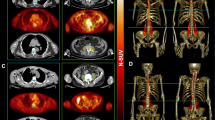

Amyotrophic lateral sclerosis (ALS) is a progressive neurodegenerative disorder with on average a 1-year delay between symptom onset and diagnosis. Studies have demonstrated the value of [18F]-FDG PET as a sensitive diagnostic biomarker, but the discriminatory potential to differentiate ALS from patients with symptoms mimicking ALS has not been investigated. We investigated the combination of brain and spine [18F]-FDG PET-CT for differential diagnosis between ALS and ALS mimics in a real-life clinical diagnostic setting.

Patients with a suspected diagnosis of ALS (n = 98; 64.8 ± 11 years; 61 M) underwent brain and spine [18F]-FDG PET-CT scans. In 62 patients, ALS diagnosis was confirmed (67.8 ± 10 years; 35 M) after longitudinal follow-up (average 18.1 ± 8.4 months). In 23 patients, another disease was diagnosed (ALS mimics, 60.9 ± 12.9 years; 17 M) and 13 had a variant motor neuron disease, primary lateral sclerosis (PLS; n = 4; 53.6 ± 2.5 years; 2 M) and progressive muscular atrophy (PMA; n = 9; 58.4 ± 7.3 years; 7 M). Spine metabolism was determined after manual and automated segmentation. VOI- and voxel-based comparisons were performed. Moreover, a support vector machine (SVM) approach was applied to investigate the discriminative power of regional brain metabolism, spine metabolism and the combination of both.

Brain metabolism was very similar between ALS mimics and ALS, whereas cervical and thoracic spine metabolism was significantly different (in standardised uptake values; cervical: ALS 2.1 ± 0.5, ALS mimics 1.9 ± 0.4; thoracic: ALS 1.8 ± 0.3, ALS mimics 1.5 ± 0.3). As both brain and spine metabolisms were very similar between ALS mimics and PLS/PMA, groups were pooled for accuracy analyses. Mean discrimination accuracy was 65.4%, 80.0% and 81.5%, using only brain metabolism, using spine metabolism and using both, respectively.

The combination of brain and spine FDG PET-CT with SVM classification is useful as discriminative biomarker between ALS and ALS mimics in a real-life clinical setting.